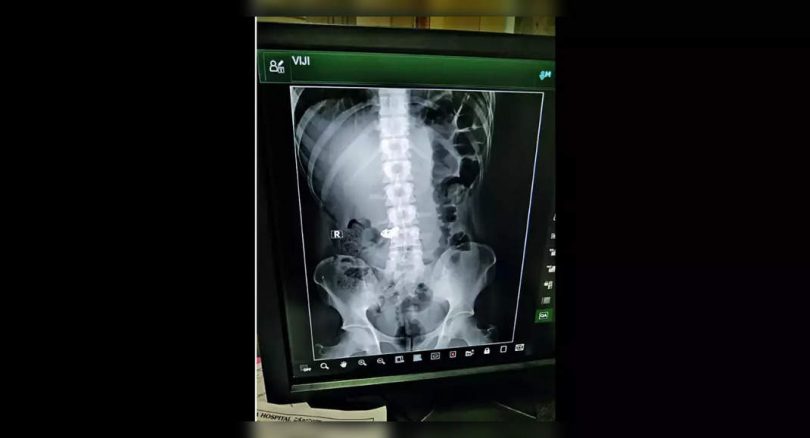

X-ray, however, shows the part trapped in his stomach.